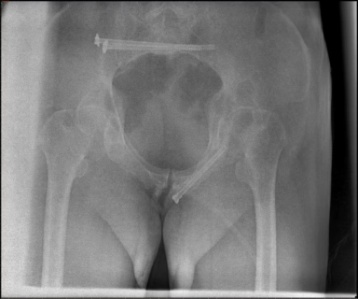

术后影像

经过术中、术后影像学检查确认,骨折复位良好,内固定位置满意。手术仅留下几个1-2厘米左右的小切口,术中出血约100ml,术后48小时患者即可在床上自主活动,现恢复良好。